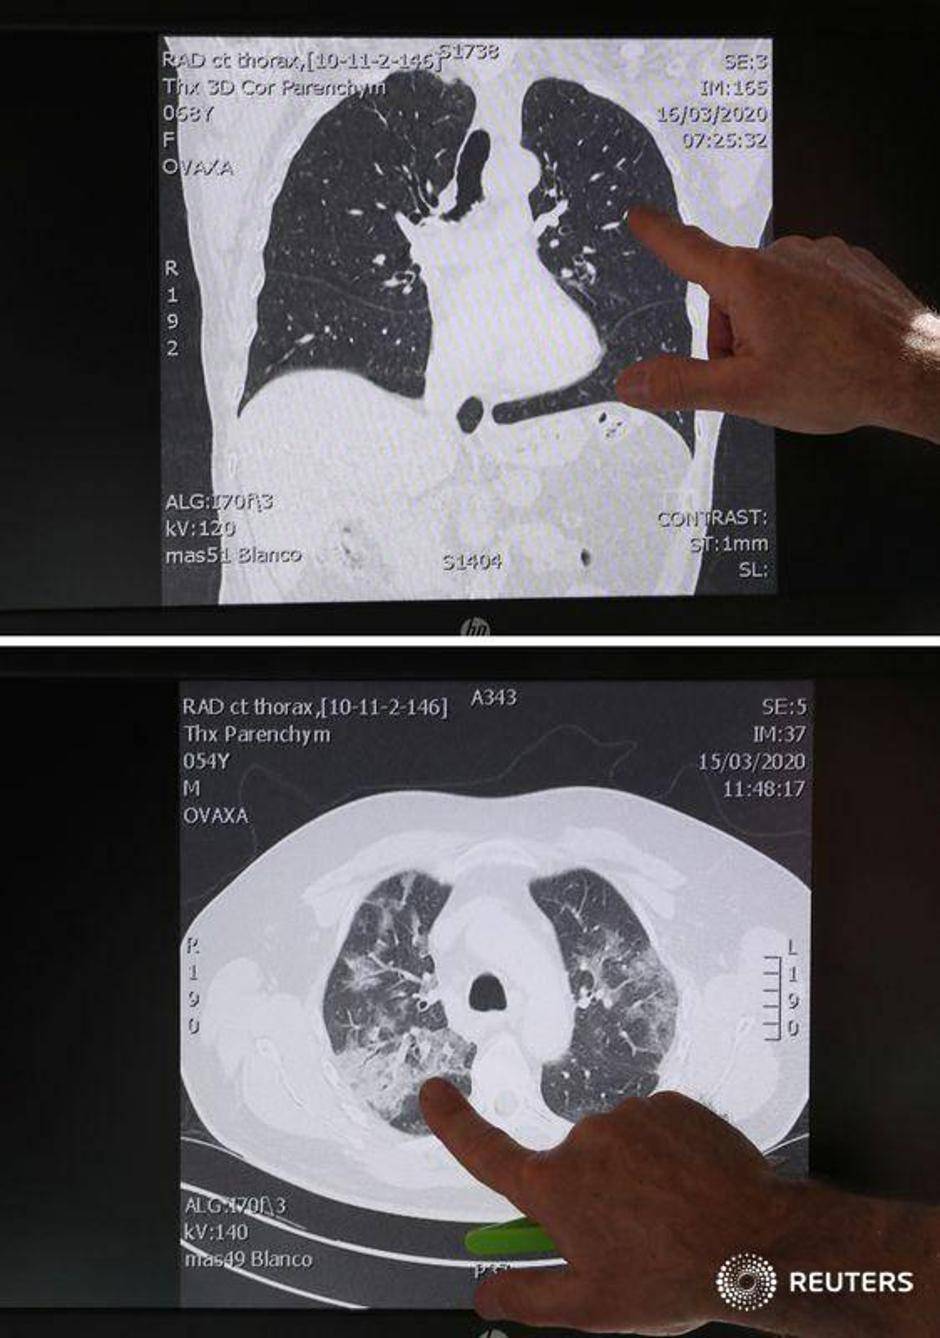

U međuvremenu, liječnik hitne pomoći u Belgiji otkrio je šokantne slike pluća 'mladih, zdravih ljudi', koje je opisao kao 'ništa strašno'. Ignace Demeyer, također je upozorio da nitko nije izuzetak što se tiče zaraze virusom.

Doktor Demeyer također je pokazao nedavne snimke pluća pacijenta s koronavirusom. U pitanju su bili mladi ljudi koji su se bavili sportom.

Prva pretraga pokazuje normalna, zdrava pluća. Drugi prikazuje vreće zraka u plućima ispunjene upalnom tekućinom, što je na trećoj slici vidljivo.

- Ti ljudi se naravno mogu još izliječiti, ali to je opasna situacija po život. A oni su ljudi koji ne puše, nemaju dijabetes ili probleme sa srcem. Oni su sportski mladi ljudi - dodao je liječnik.